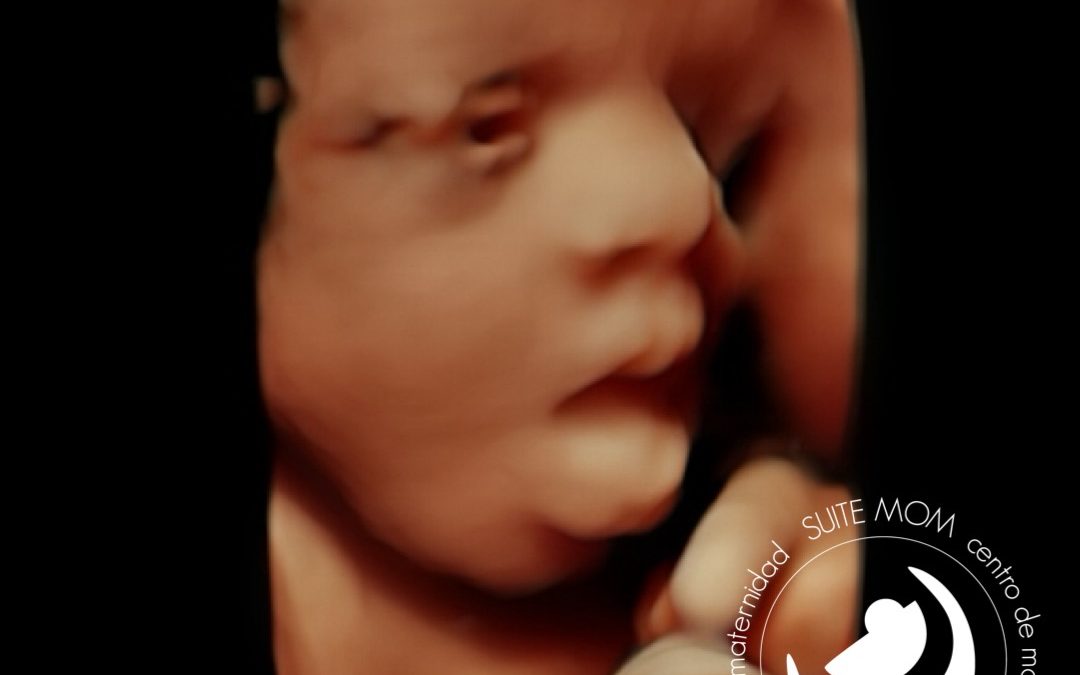

Ecografía emocional 5D. 30 semanas de gestación.

Ecografía emocional 5D, Bebé de 30 semanas de embarazo. Realizada en nuestro centro de Maternidad, Suite Mom. San Fernando de Henares, Madrid.

En esta ecografía podemos ver a un bebé de 30 semanas de gestación. Está on los ojitos abiertos, y sacando la lengua, en la parte inferior derecha podemos ver parte de la mano izquierda en forma de puño, y levemente difuminado parte del cordón umbilical!